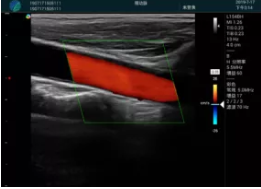

頸動(dòng)脈血流充盈飽滿,無外溢